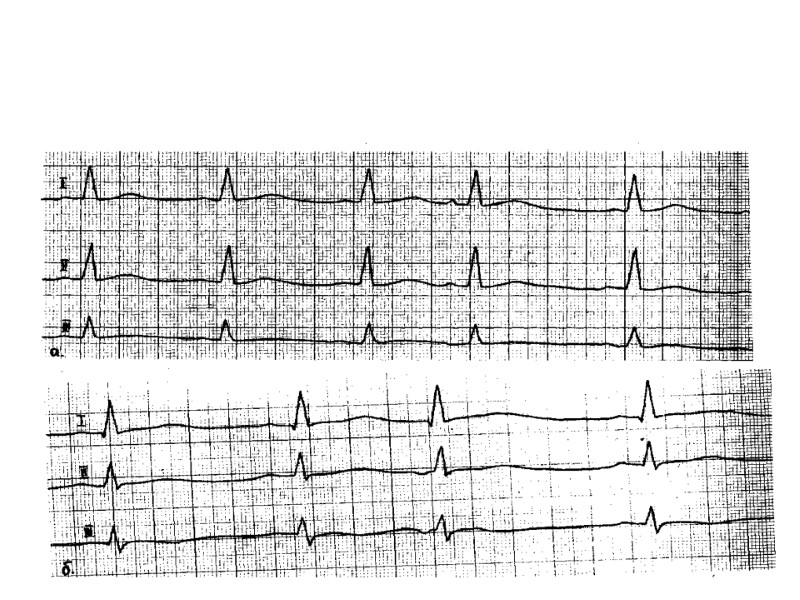

Суточное мониторирование ЭКГ по Холтеру При анализе суточной записи ЭКГ осуществляется Автоматический анализ нарушений ритма сердца: Желудочковых аритмий –экстрасистол, пароксизмов ЖТ Наджелудочковых аритмий экстрасистол, пароксизмов СВТ Пауз Автоматический анализ изменений сегмента ST Диагностика ИБС